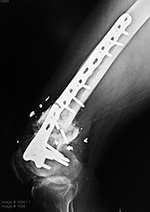

| Failure of fracture fixation due to ambulating against advice |

| Male patient with proximal tibia and fibula fractures treated by intramedullary nail and supplemental one-third tubular plate. Initial intraoperative fluoroscopic AP and lateral images (left two images) show the plate (arrow on lateral image). The patient ambulated against advice and was lost to follow-up. Two months later he again presented (right two images) to the clinic. There is now tibia fracture migration, and the proximal medial to lateral interlocking screw has backed out (AP view). The lateral view demonstrates fracture displacement with flexion deformity. The nail has troughed outside the proximal anterior tibia and is sitting within the soft tissues. The supplementary plate is broken, there is a broken interlocking screw, and abundant fracture callus is present. |